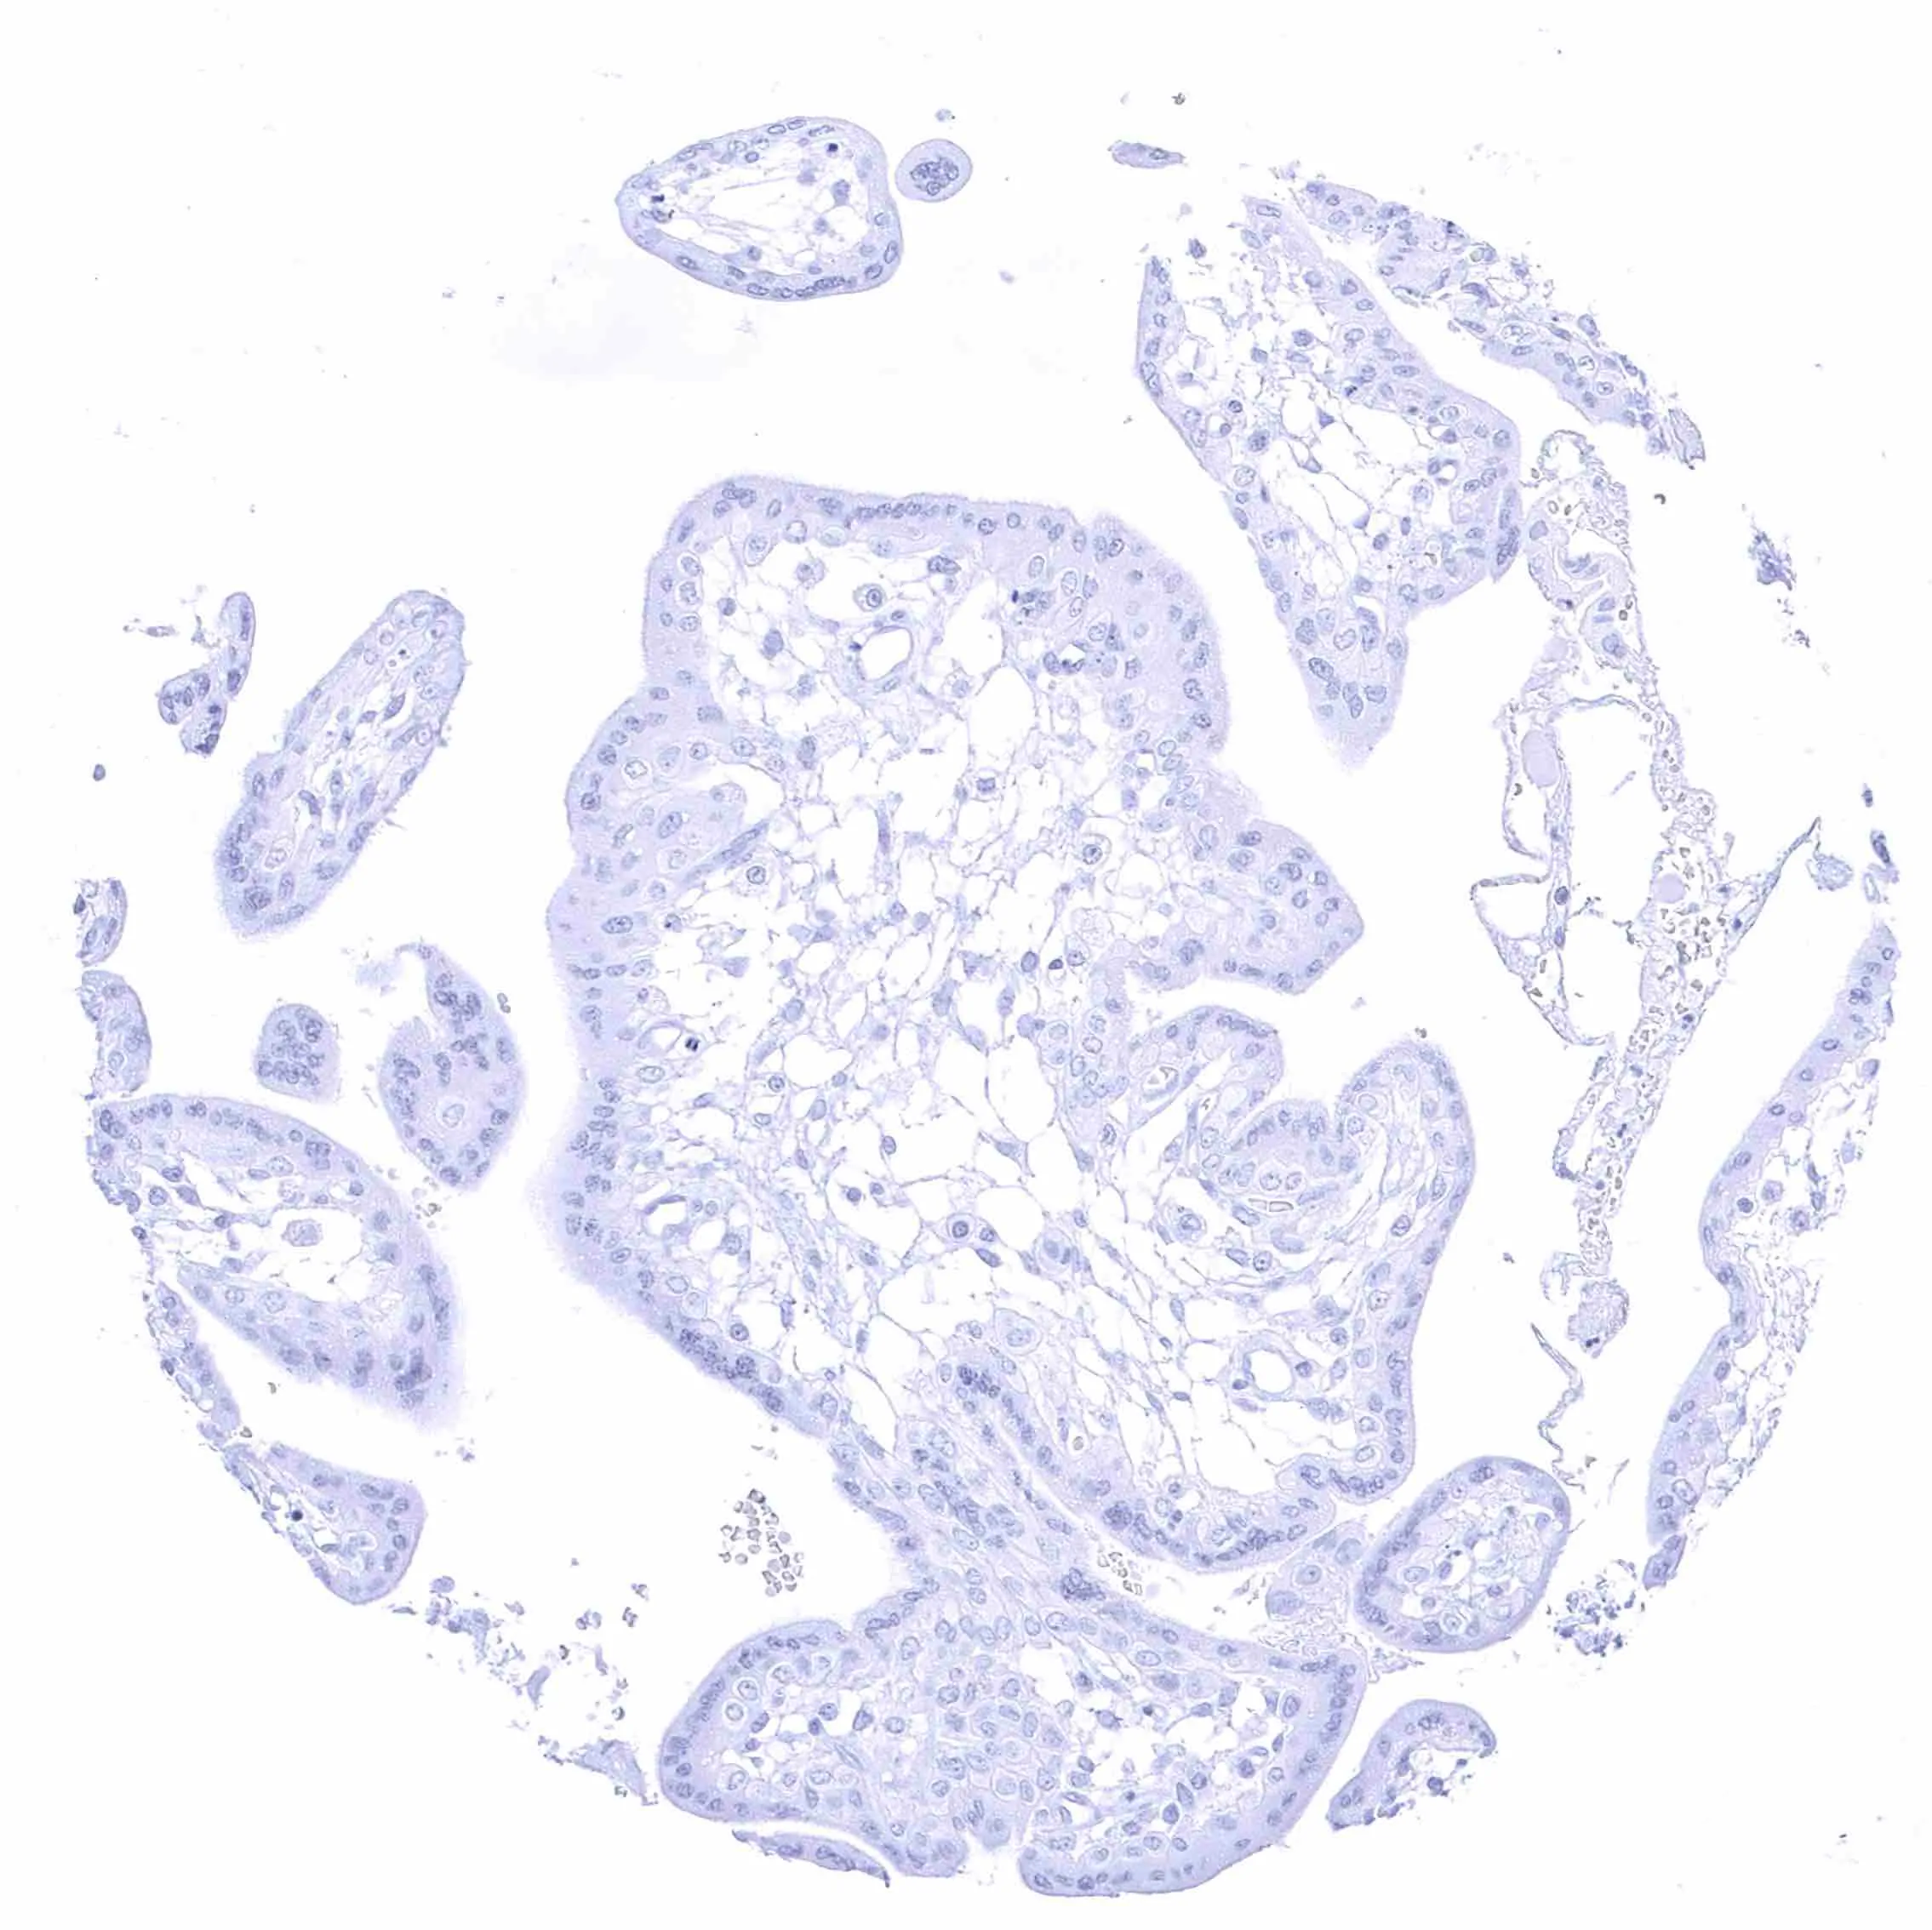

Placenta, early